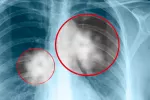

Un nuevo fármaco, eficaz contra un tipo de cáncer de pulmón agresivo